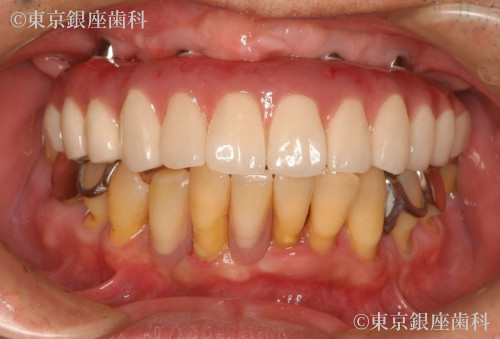

2型糖尿病の治療を経て歯周病の進行によって失われた咬合機能をワンデイインプラントにより回復。ただし費用の都合により上顎のみ手術。患者の希望により残存歯の多い下顎は義歯を使用した例。

After

今回は上顎のみを希望。動揺の激しい残存歯を抜歯、即時にインプラント4本の埋入と仮歯の固定で審美面の回復も行った。

下顎の動揺歯抜歯後の欠損部には作成した義歯を使用。

2型糖尿病の治療と口腔機能の大幅な改善により全身の健康状態が回復できた。